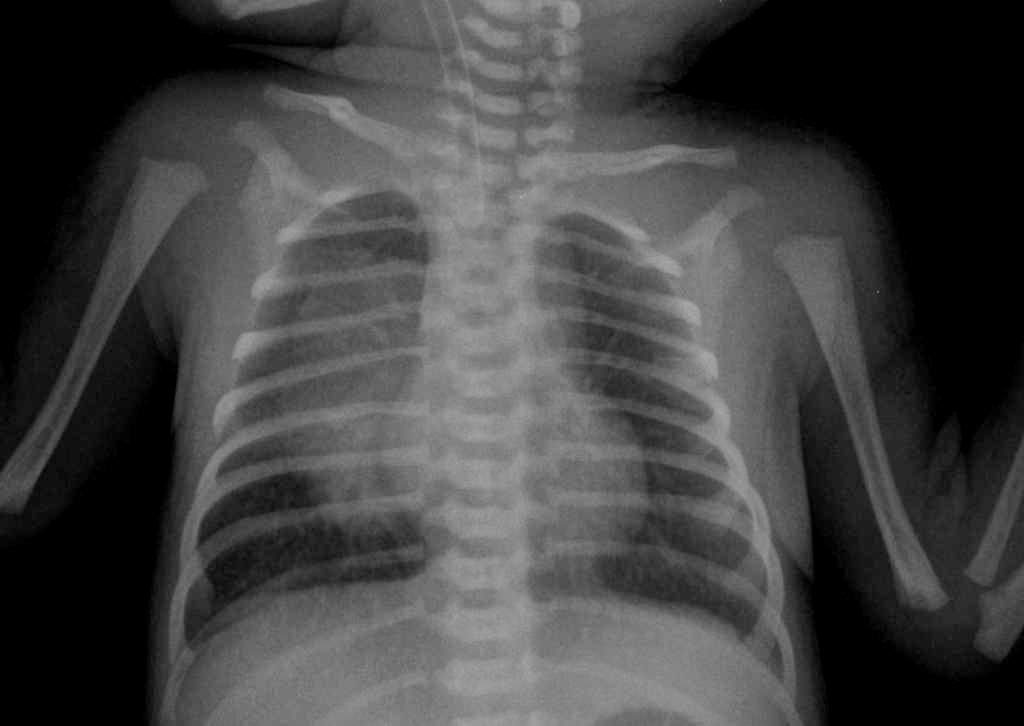

Диагностика

Для диагностирования пневмонии важное значение имеет рентгенография

В целях диагностирования у новорождённого пневмонии врач проводит следующие мероприятия:

- Инструментальные исследования:

- рентген грудной клетки (рентгенография);

- эхокардиография;

- КТ (компьютерная томография).